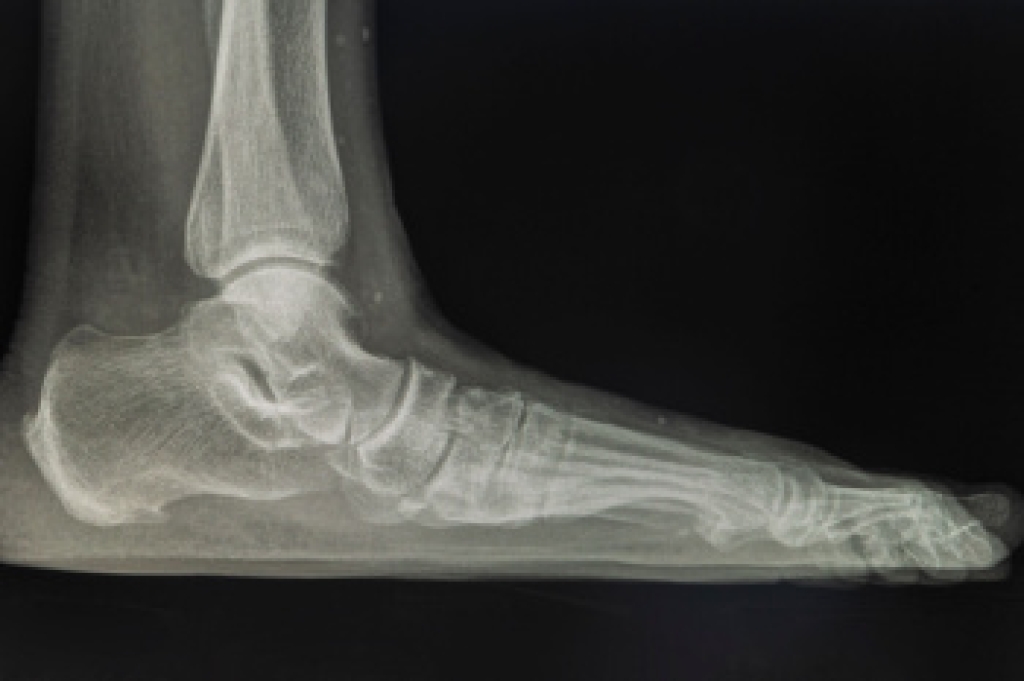

Wearing high heels may enhance height and appearance, but frequent use can lead to significant foot problems. The unnatural position of the foot places pressure on the toes and forefoot, often causing bunions and hammertoes. The elevated heel strains the Achilles tendon, leading to Achilles tendonitis, and increases tension on the plantar fascia, resulting in plantar fasciitis. Over time, these conditions can cause chronic pain and limit mobility. A podiatrist can assess the damage, relieve discomfort, and recommend supportive footwear or custom orthotics. If you have pain from wearing high heels, it is suggested that you visit a podiatrist who can treat various foot conditions, and guide you on how to choose heels that are better for your feet.

- Plantar Fasciitis